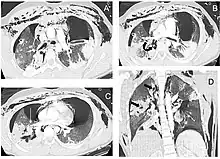

| Reconstruction of the trachea and bronchi with x-ray computed tomography showing disruption of the right main bronchus with abnormal lucency (arrow)[1] | |

- 1 2 3 Le Guen M, Beigelman C, Bouhemad B, Wenjïe Y, Marmion F, Rouby JJ (2007). "Chest computed tomography with multiplanar reformatted images for diagnosing traumatic bronchial rupture: a case report". Critical Care. 11 (5): R94. doi:10.1186/cc6109. PMC 2556736. PMID 17767714.